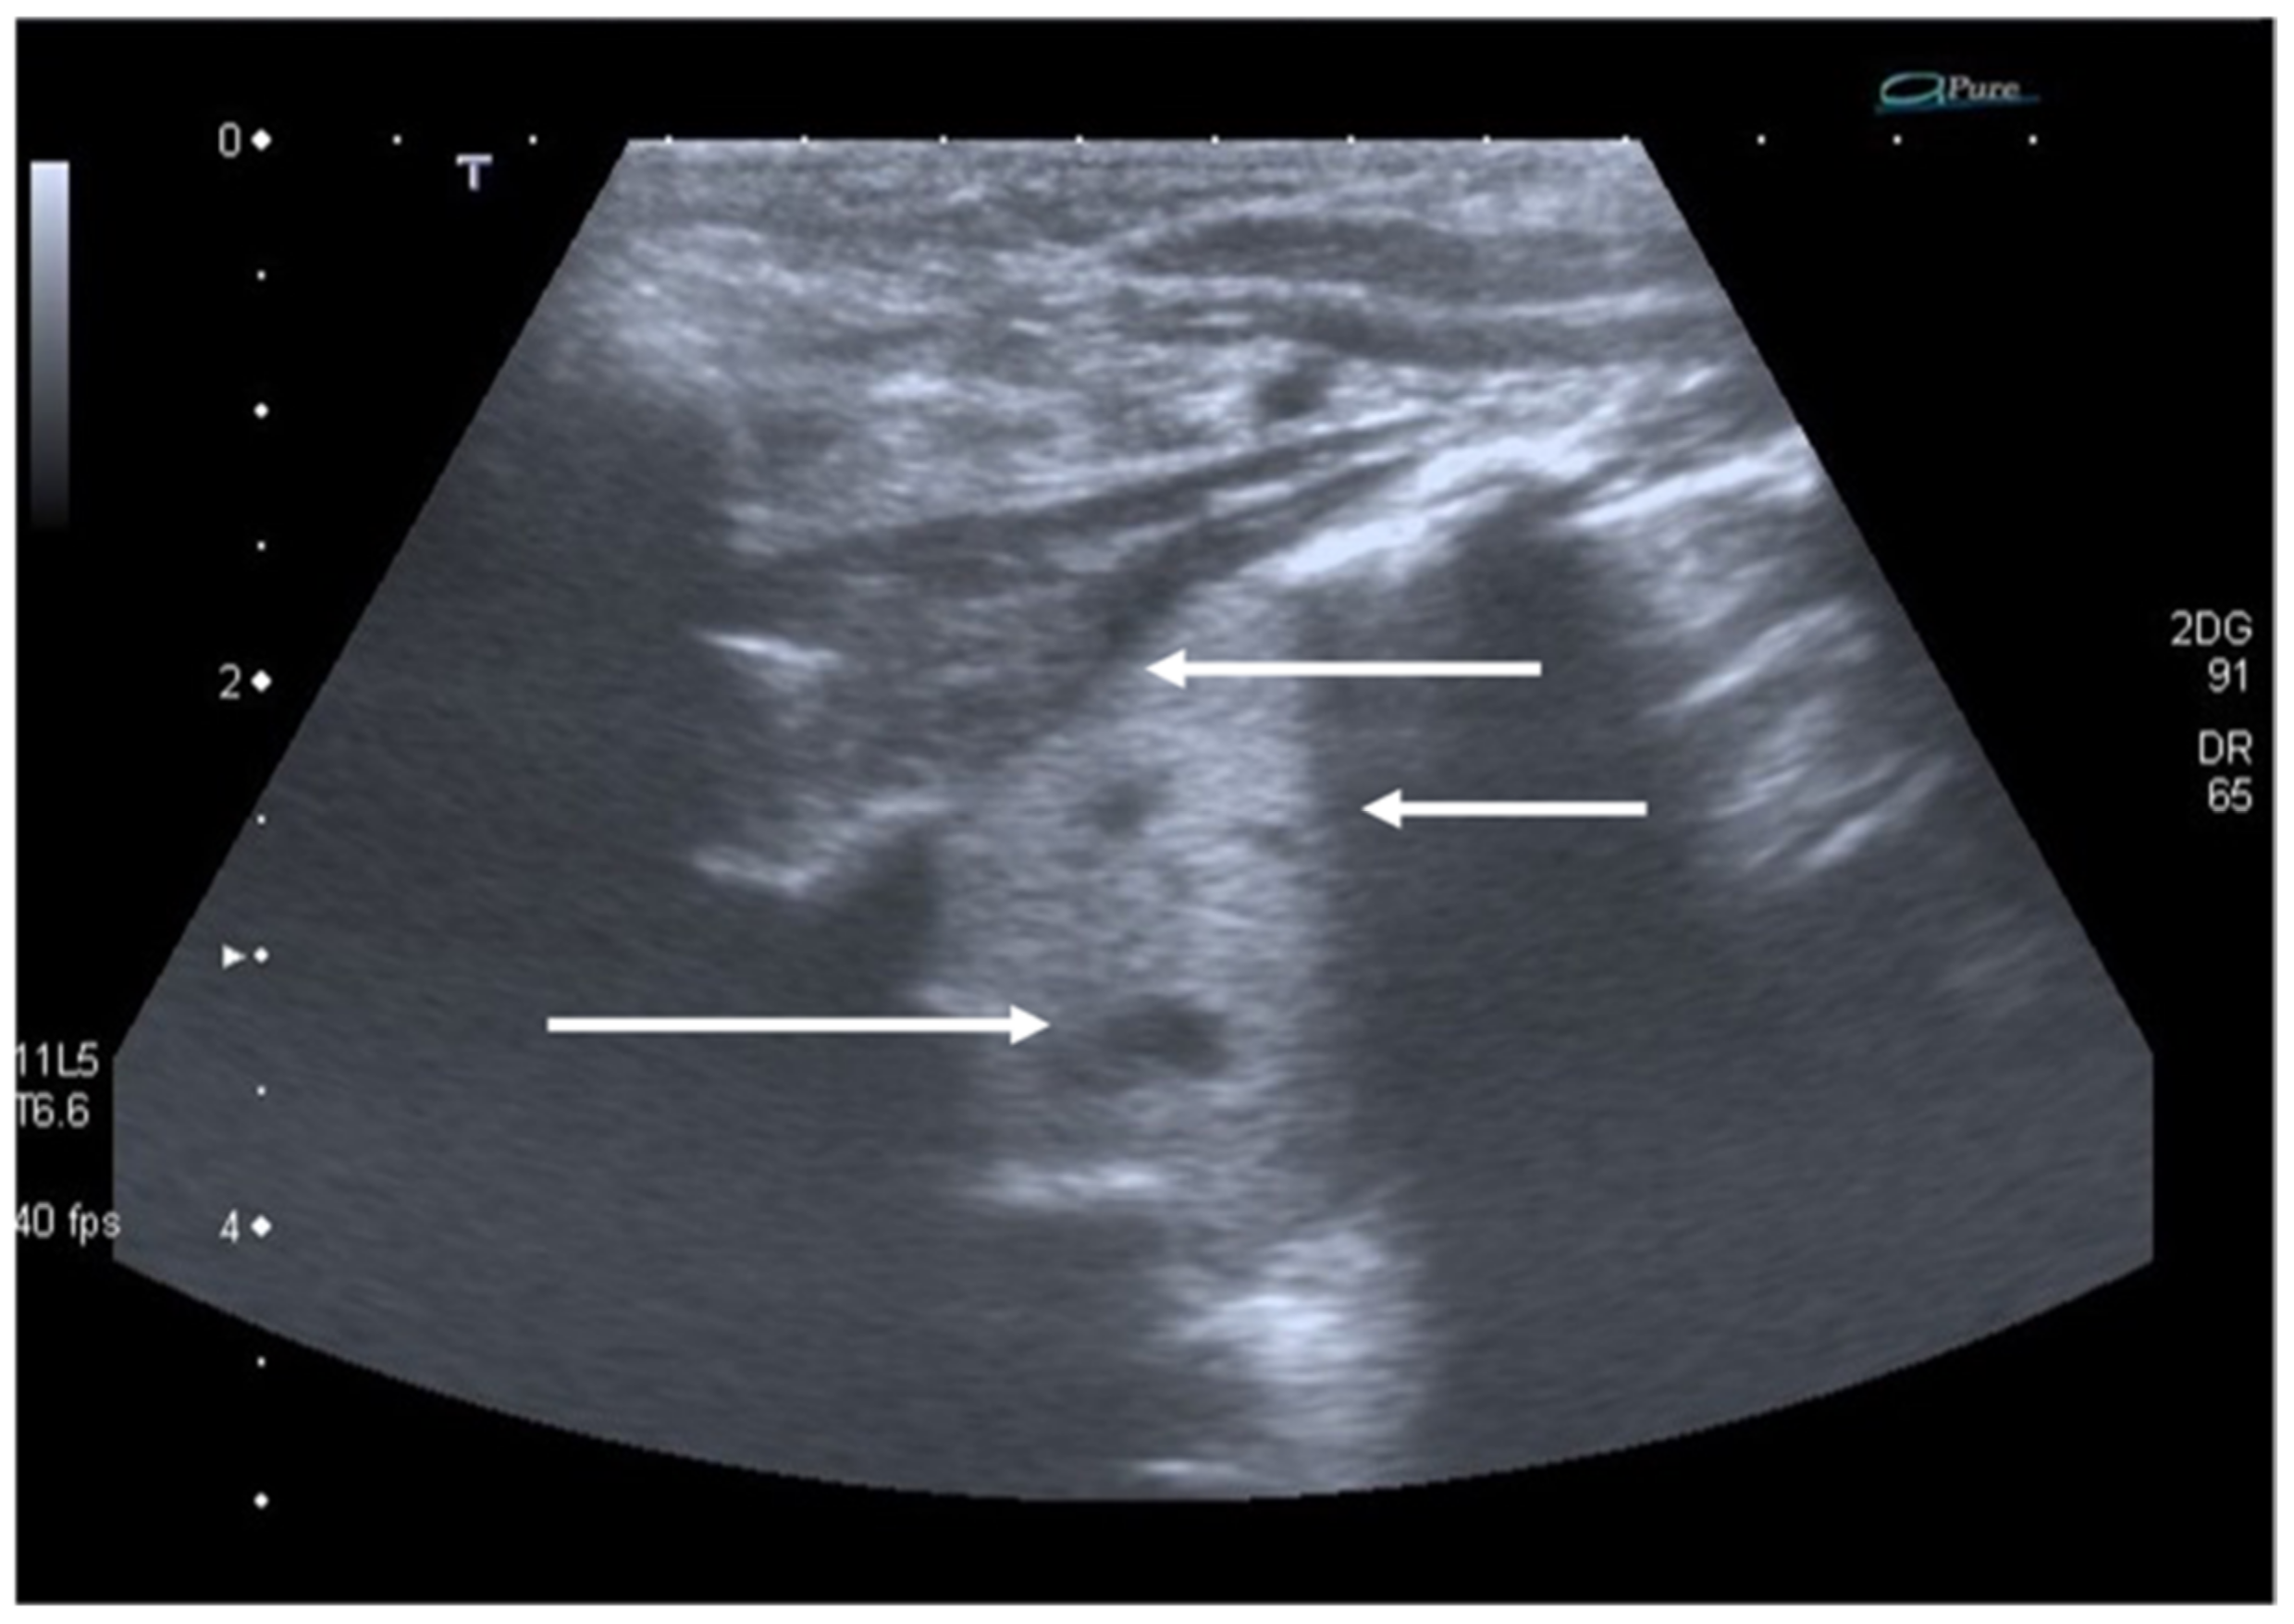

- Diagnosis and follow-up of pediatric lung infectious diseases (namely bronchiolitis and pneumonia) and lung complications (such as pneumothorax, pleural effusion and lung abscess);

8. Pneumothorax, Pleural Effusion Empyema and Lung Abscess

- Grimberg, A.; Shigueoka, D.; Atallah, A.N.; Ajzen, S.; Iared, W. Diagnostic accuracy of sonography for pleural effusion: Systematic review. Sao Paulo Med. J. 2010, 128, 90–95. [Google Scholar] [CrossRef] [Green Version]

- Soni, N.J.; Franco, R.; Velez, M.I.; Schnobrich, D.; Dancel, R.; Restrepo, M.I.; Mayo, P.H. Ultrasound in the diagnosis and management of pleural effusions. J. Hosp. Med. 2015, 10, 811–816. [Google Scholar] [CrossRef] [PubMed] [Green Version]

- Prina, E.; Torres, A.; Carvalho, C. Lung ultrasound in the evaluation of pleural effusion. J. Bras. Pneumol. 2014, 40, 1–5. [Google Scholar] [CrossRef] [Green Version]